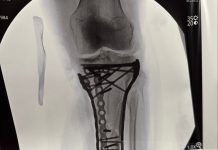

La omisión de rutinas preventivas puede derivar en cirugías o rehabilitación prolongada, comprometiendo la salud y la carrera de los deportistas olímpicos

Ignorar las rutinas preventivas puede tener consecuencias severas: la pérdida de estabilidad articular impide competir con seguridad, y intentar esquiar con un ligamento cruzado anterior debilitado incrementa la probabilidad de lesiones complejas. En casos graves, la cirugía o una rehabilitación extensa pueden ser necesarias para recuperar la funcionalidad y evitar recaídas.